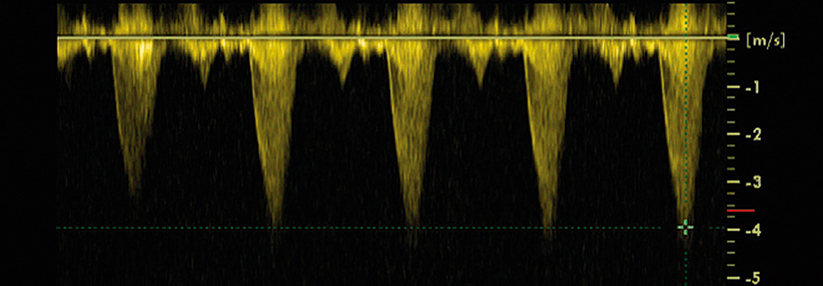

Vor der hochgefährlichen Schwangerschaftskardiomyopathie scheint es einen einfachen Schutz zu geben: eine Kurztherapie mit dem Prolaktininhibitor Bromocriptin.

Die Kardiomyopathie, die gegen Ende der Schwangerschaft bis etwa ein halbes Jahr nach Entbindung auftreten kann, stellt ein hohes Risiko dar. Viele Patientinnen behalten eine persistierende Pumpschwäche zurück, die Letalität liegt bei knapp 1,5 %. Außerdem ist jede Frau, die schon einmal eine solche Komplikation durchgemacht hat, bei der nächsten Gravidität wieder gefährdet.